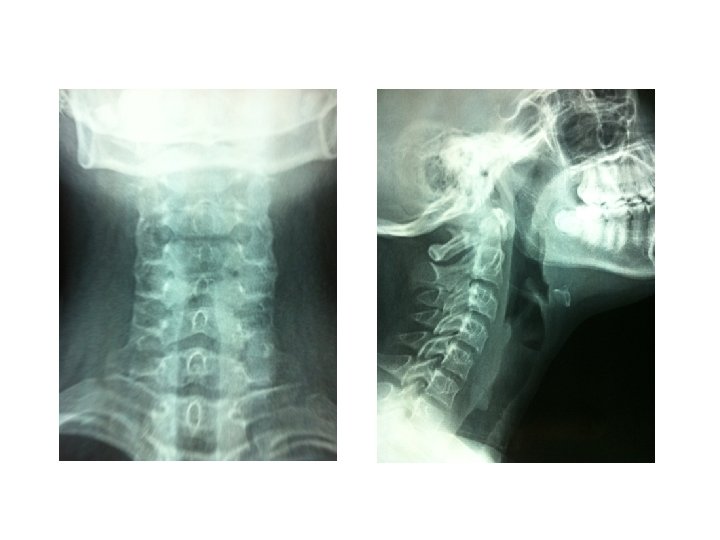

• Examination findings – Respiratory system : Stridor + – Other systems : Normal • Suspected diagnosis: – Post intubation tracheal stenosis

• Histopathological examination – Inflammatory myofibroblastic tumour of the trachea